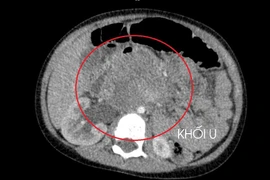

Khi tiếp nhận, bệnh nhân được thăm khám lâm sàng, làm xét nghiệm máu và các kỹ thuật chẩn đoán hình ảnh. Kết quả ghi nhận bệnh nhân dương tính với sán lá gan và giun đũa chó mèo, đồng thời phát hiện ổ áp xe gan kích thước gần 5 cm, kèm tăng bạch cầu ái toan và các chỉ số viêm.

Theo bác sĩ Hương, ổ áp xe gan có kích thước khá lớn, nếu bệnh nhân đến muộn hoặc không được điều trị kịp thời, nguy cơ vỡ ổ áp xe và nhiễm khuẩn huyết là rất cao.

Sau khi đánh giá toàn diện, bệnh nhân được chỉ định phác đồ điều trị gồm chọc hút ổ áp xe, sử dụng thuốc đặc hiệu diệt ký sinh trùng, phối hợp kháng sinh kiểm soát nhiễm trùng và theo dõi sát bạch cầu ái toan, men gan cùng các chỉ số viêm.

Trong quá trình điều trị nội trú và theo dõi ngoại trú, bạch cầu ái toan của người bệnh trở về mức bình thường, ổ áp xe gan thu nhỏ, không còn dịch mủ.